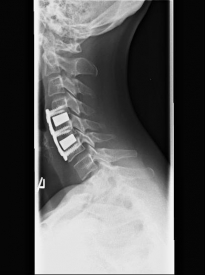

MRI with lateral reconstruction of the cervical spine and a lateral postoperative radiographic check. On the left, an hourglass-shaped constriction of the spinal cord can be seen. The right image shows the condition after surgical decompression and stabilization.